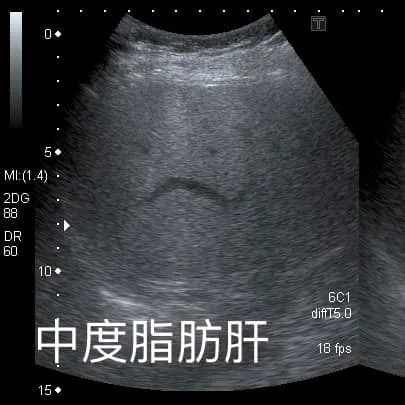

錢政弘在臉書發文分享此案例說,這位阿姨去年就診時,有中度脂肪肝現象,但近日她回診時瘦了快10公斤,肝臟完全恢復正常,脂肪消失了。他請教阿姨減重成功有何秘訣?沒想到阿姨回答:「我就『少吃水果』!」讓他非常驚訝。

他進一步問阿姨得知,對方去年體重66公斤,長期有高血壓、中度脂肪肝,而她很愛吃水果,一天可以吃掉整顆鳳梨,但發現血糖數值持續上升後,決定要減少吃水果,只吃原本的2成左右,結果體重就逐步下降到51公斤,最近才復胖到56公斤,而她先生同樣愛吃水果,跟著她一起改變吃水果習慣後,從80公斤瘦到60多公斤。阿姨還說,運動健走對她來說沒有減重效果,「還是少吃差最多!」